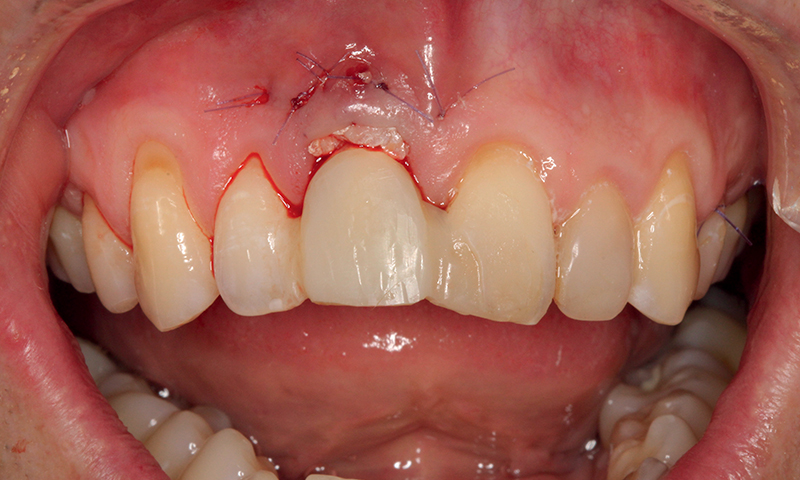

Fig. 14 (caso 3) - Decordo clinico dell'innesto di tessuto connettivo dopo l'inserimento dell'impianto

Caso 3: Un paziente maschio subiva un trauma durante l'infanzia e si presentava con una fistola associata al dente 11 e un difetto della cresta alveolare vestibolare. Il paziente era sottoposto a posizionamento immediato di un impianto SDS. In questo caso, l'aumento veniva combinato con il prelievo di tessuto connettivo subepiteliale (SCTG) dal palato, attraverso una singola incisione, tunnellizzazione buccale e inserimento dell’innesto. I successivi appuntamenti di follow-up rivelavano il successo della preservazione della cresta alveolare vestibolare, e della guarigione dei tessuti molli attorno all'impianto. L'osteointegrazione avveniva senza problemi e si poteva iniziare la pianificazione della corona definitiva. Questo caso era seguito per 5 anni e anche dopo questo periodo il contorno alveolare era estremamente soddisfacente. La guarigione e la gestione dei tessuti molli erano adeguate, suggerendo come l'applicazione dell'innesto di tessuto connettivo abbia contribuito positivamente al risultato estetico (Fig. 11-17).